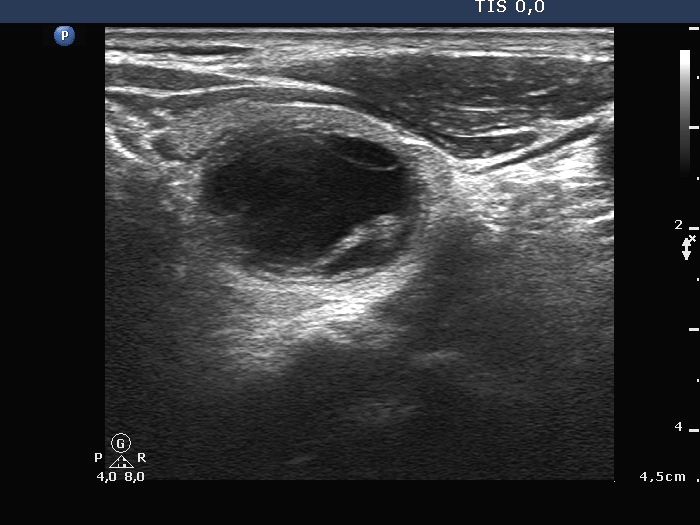

Papillary carcinoma - Case 10. (ultrasound picture 4)

Upper part of the left lobe, another horizontal view. This is the lower section of the papillary carcinoma.